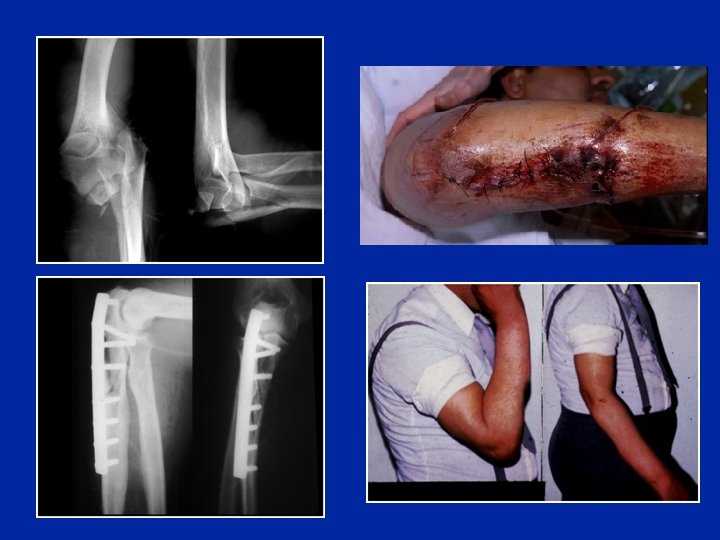

Fracture de Monteggia Fracture du cubitus + Luxation de la tête du radius

Diagnostic radiologique de la luxation du radius - L’axe du radius doit normalement passer au centre du condyle - Faire des radios comparatives luxation réduction

Traitement de la fracture de Monteggia - Réduction - Ostéosynthèse “anatomique“du cubitus - Le radius est alors stable